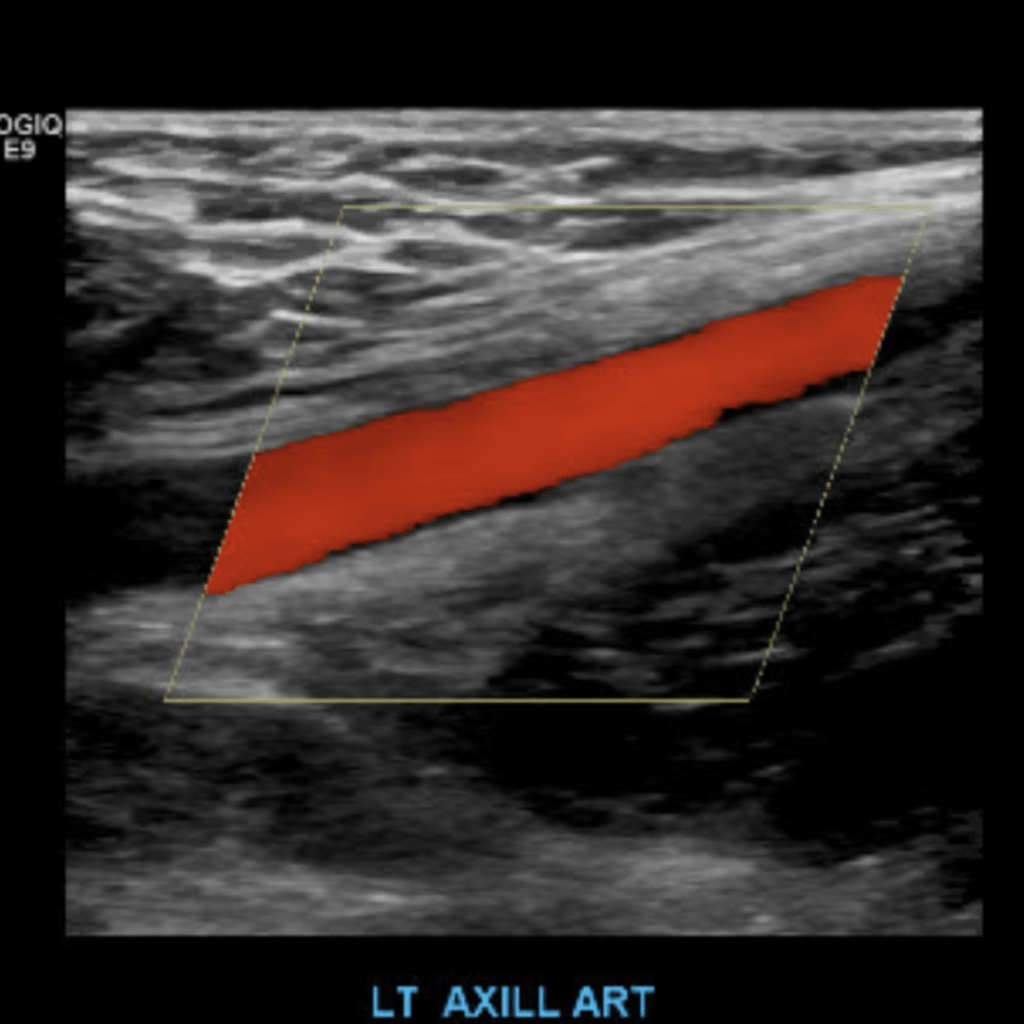

The subclavian artery arises from the brachiocephalic artery on the right and off of the aortic arch on the left. This artery further divides into the axillary, brachial, radial, ulnar, palmar and digital arteries respectively.